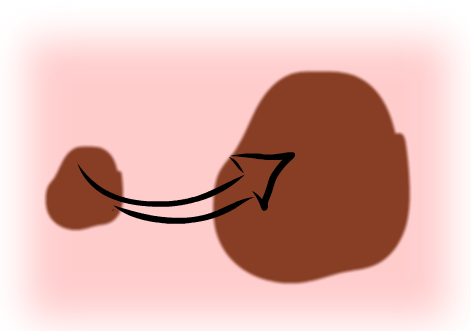

- E - Vývoj (Evolution) - znaménko se mění – roste, svědí, krvácí.